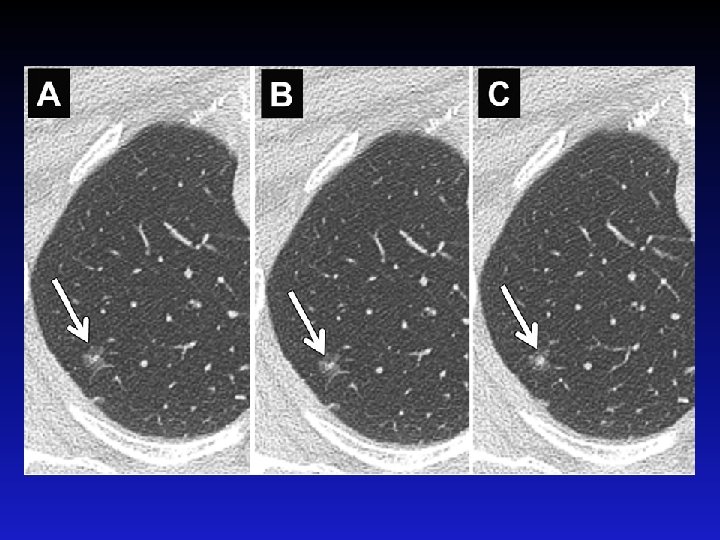

Serial Imaging to Assess Growth (1 mm cuts) Naidich D P et al. Radiology 2013; 266: 304 -317

Rapid Enlargement of a GGO Naidich D P et al. Radiology 2013; 266: 304 -317